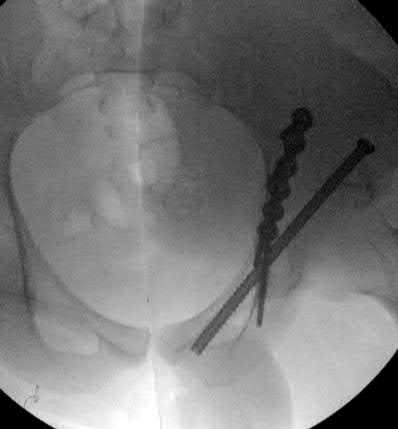

A 12-year-old obese boy presents with vague left thigh and knee pain. He is diagnosed with a Slipped Capital Femoral Epiphysis (SCFE) as seen in similar clinical scenarios.

During percutaneous in-situ fixation, unrecognized penetration of the guide wire into the hip joint occurs. What is the most likely specific complication resulting from this technical error?

Explanation

Chondrolysis is a severe complication of SCFE characterized by rapid destruction of the articular cartilage. While it can occur idiopathically, its most established iatrogenic cause is unrecognized intra-articular hardware penetration. The 'approach-withdraw' fluoroscopic technique is required during pinning to assure pins are entirely intraosseous. Avascular necrosis (AVN) is usually due to damage to the epiphyseal blood supply (retinacular vessels) secondary to the initial displacement, forceful closed reduction, or posterosuperior pin placement.